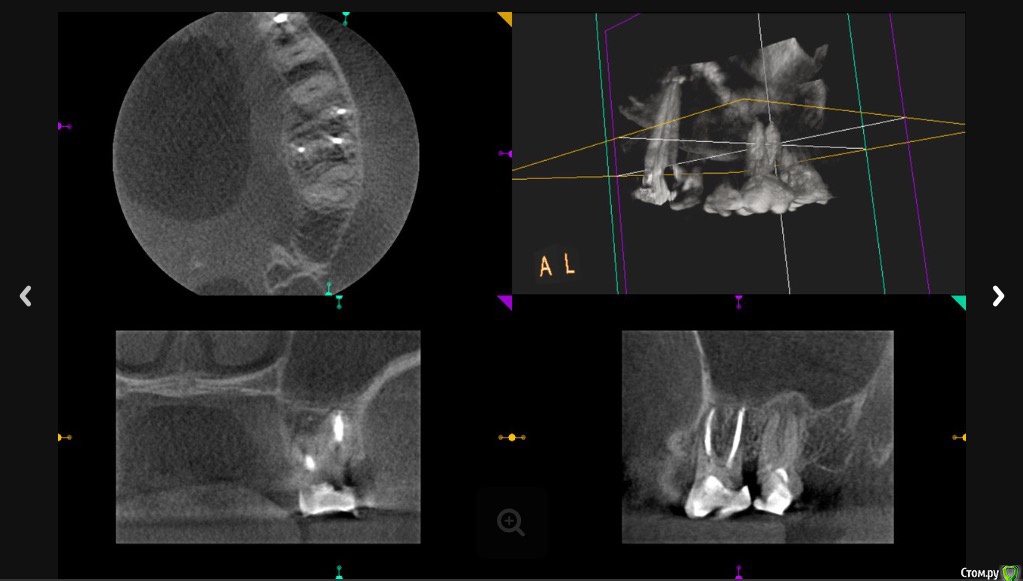

Л Ю С Я Опубликовано 5 декабря, 2016 Поделиться Опубликовано 5 декабря, 2016 Полечили гаиморит без ЛОР. Срок наблюдения 6 месяцев. Теперь на очереди 2.7 5 Ссылка на комментарий

Л Ю С Я Опубликовано 5 декабря, 2016 Поделиться Опубликовано 5 декабря, 2016 КлассДа, очень показательно. Хотя пациентка сначала не верила в успех, поэтому от лечения 2.7 отказалась. 10 лет мучений, не знаю ,почему лор не заподозрил одонтогенный. Пришла начитавшись Интернета про причины гайморита. Видимо не зря читала))) Ссылка на комментарий

Л Ю С Я Опубликовано 5 декабря, 2016 Поделиться Опубликовано 5 декабря, 2016 Все стандартно, растворы хлорка, эдта,апексы пал-50, бук-40-45, от рд -0.5, кальций был 2 раза, петенси получено везде,первый раз во время обработки случайно вышла за апекс небного, как полилось.. ((((Минут 30 сопли. Симптомы ушли. Задышала. Через 2 недели как то влажно, ещё кальций, через 2 недели постоянная обтурация : пал- сквирт, бук- волна. Перед обтурацией ХГБ. Пациентка от коронки категорически отказывалась, сделали композитный оверлей. Сейчас собираемся перебирать 2.7, потом все равно заставлю коронки сделать. Кстати, заметила, если эндо сделано удачно, в пазухе достаточно быстро все восстанавливается 1 Ссылка на комментарий

Сева северный Опубликовано 6 декабря, 2016 Поделиться Опубликовано 6 декабря, 2016 Степень вовлеченности пазухи.Тут вообще трэш,господа Степень вовлеченности пазухи.Тут вообще трэш,господа! ... Под вовлеченностью , я понимаю ответ пазухи на воспаление исходящее от зуба располагающегося ... в непосредственной близости к ней..или интимно входящего неё. Для сравнения два моих случая, где зубы находились в непосредственной близости к синусу, но его реакция, была разной. Кстати.... воспаление .... ушло благодаря, проведенному эндолечению. Ссылка на комментарий